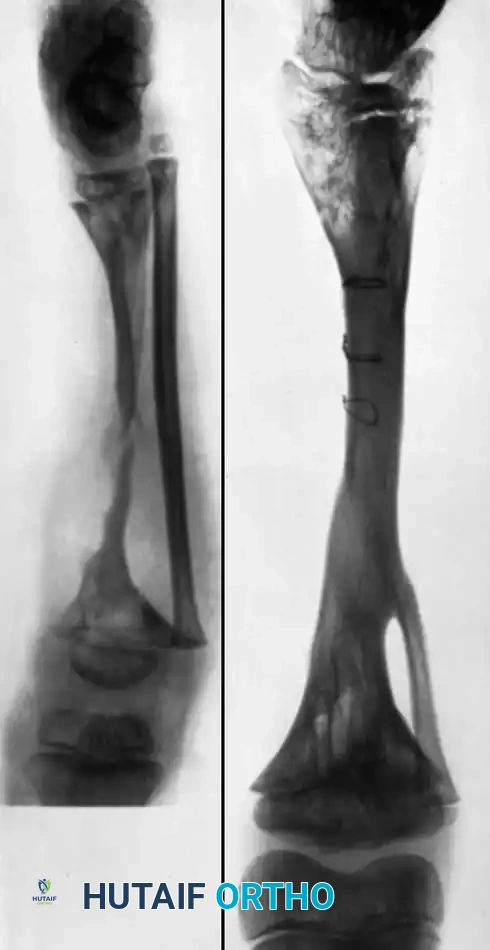

Fig. 16-19 A, Defect in the tibia of a 4-year-old child after treatment of acute osteomyelitis by removal of a large sequestrum before sufficient involucrum had formed to ensure the continuity of the bone. B, After transplantation of the fibula to bridge the defect.